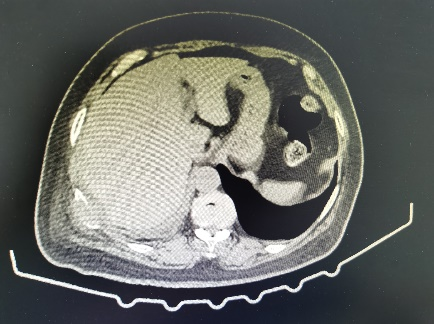

51岁的辛先生和74岁的汪女士均为我院胸外科的肺癌术后随访6年的老患者,辛先生在上月体检时行胸部CT检查发现自己的右侧肺部竟再次长出一个直径约1.5cm的混合磨玻璃结节,而汪女士在近1年来出现右侧胸腹壁疼痛症状,复查胸部CT及骨扫描发现肋骨及胸椎癌转移。出现新发结节令辛先生寝食难安,查出骨转移更是令汪女士惶恐失措。为寻求治疗,两位患者再次来到我院胸外科李少民教授处就诊。

考虑到两位患者均经历过手术的疼痛及术后化疗的折磨,本次治疗旨在消除病灶减轻患者痛苦,提高生存质量。为此,经过详细地评估及充分地沟通后,李少民教授为患者制定了“冷冻消融”的治疗方案,其中辛先生的病灶位于肺野外围适合CT引导下冷冻消融,汪女士的病灶位于肋骨及椎体,更适合超声引导下冷冻消融。

经过周密术前准备后,由胸外科李少民教授、马跃峰副主任医师、马震川主治医师,在放疗CT定位室、超声科的严密配合下为两位患者分别实施了CT引导下、超声引导下的肿瘤冷冻消融术。经过反复地定位及精准地穿刺,团队顺利将冷冻消融针置入肺结节中,经过重复2个循环的“冷冻-复温”,肿瘤经冷冻消融后变成了“冰块”。手术历时约半个小时,患者反应良好,没有明显疼痛及胸闷气短。